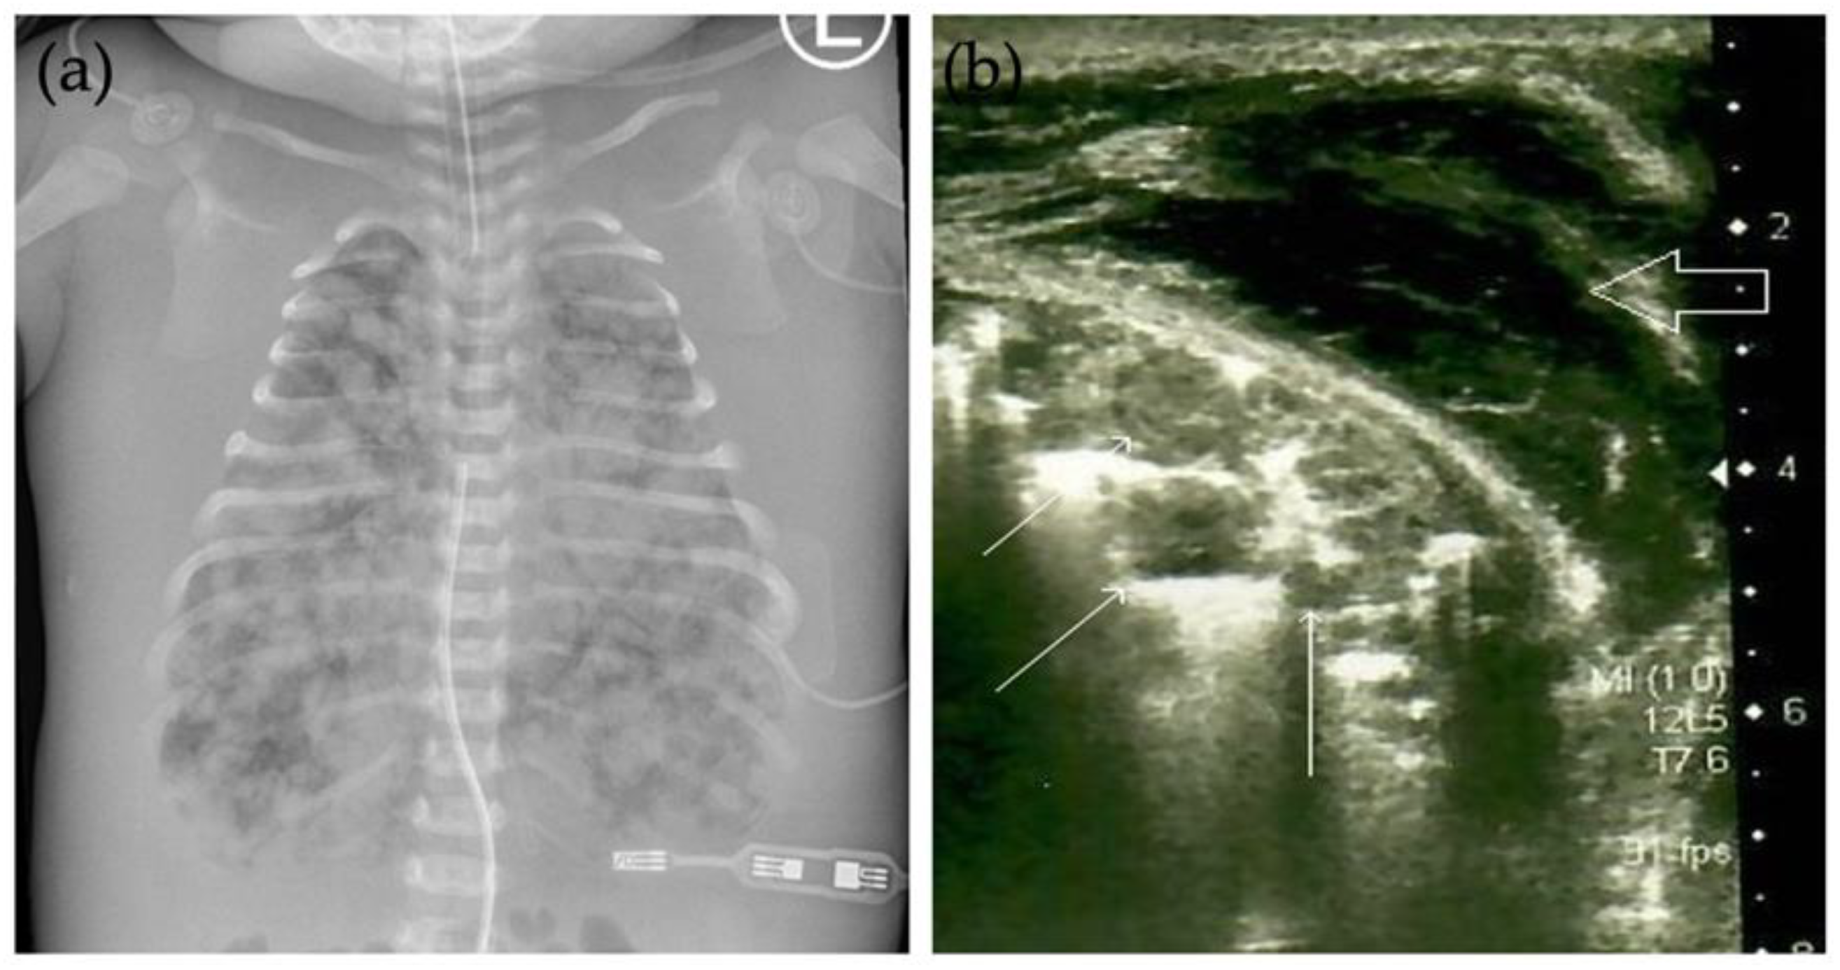

The patient was a full-term new-born male (4110 g) with hydrops fetalis, delivered by emergency caesarean section due to the pelvic insertion, polyhydramnios, ascites, and meconium in the amniotic fluid. The mother’s past medical and obstetric history included an uneventful pregnancy with a healthy female and an abortion at 6 weeks’ gestation. The Apgar scores of the neonate in the first, fifth, and fifteenth minutes were 1, 2, and 4, respectively. Immediately after birth, he required intubation and mechanical ventilation. The patient was bradycardic (85 bpm) and hemodynamically unstable; therefore, vasoactive support, along with a surfactant and antibiotics (ampicillin, gentamicin), was introduced in the intensive care unit. A chest radiograph disclosed multiple round lesions of various sizes diffusely involving the entire lung, which are extremely rare in neonates (Figure 1a). Their diameter was up to 8 mm. It was not possible to determine whether these were fluid or soft tissue changes by radiography; hence, ultrasonography of the lung was performed which showed that the multiple round nodules within the lung parenchyma were solid in nature (Figure 1b). There was no pleural effusion. Ultrasonography of the head discovered mild cerebral oedema, indicating mild hypoxic-ischemic encephalopathy, and ultrasonography of the abdomen was undertaken for assessment of the abdominal organs, which appeared normal. Biochemical analysis revealed elevated levels of liver enzymes including aspartate transaminase and gamma-glutamyl transferase, disturbances of blood coagulation tests with elevated D-dimer, and decreased thrombocyte levels. The neonate also had metabolic acidosis (pH = 7.11) with increased blood lactate concentrations, hence bicarbonate was introduced. The aforementioned coagulopathy was corrected and, due to anuria and the unclear aetiology of the disease, peritoneal dialysis was initiated.

Radiologic findings of IM are not specific. The vast majority of IM with only lung’s involvement present as a solitary nodule of various sizes on radiography [15,16]. The case presented here is unique in its extensive involvement of the lung, resembling a metastatic disease on chest radiograph. Ultrasonography of the lung showed multiple round hypoechoic solid nodules within the lung parenchyma, which were hypovascular on Doppler examination. Although this appearance is not specific for IM, the nodules were similar in appearance to those previously described by other authors [17]. Ultrasonography can be a useful technique even for prenatal detection of the tumours; however, to the best of our knowledge, only scant reports exist on prenatally diagnosed IM with ultrasonography [18]. In our case, the routine prenatal US in the first and second trimester showed no abnormalities. Due to the also unremarkable clinical surveillance of pregnancy, a follow-up prenatal US was not scheduled. It is, however, remarkable that the majority of prenatal cases have been discovered later in the third trimester [18]. Despite the autopsy findings of myofibromas in several visceral organs (i.e., heart, small and large intestine), they were not visualized by the US examinations. It is also noteworthy that, at the time of the examinations, the diagnosis of generalised IM has not been yet settled upon; therefore, the examinations were not specifically performed to search for minor tumours in all various locations [18]. Bones are also often involved in multicentric IM with the skull, tibia, femur, spine, and ribs being the most common locations, usually appearing on radiographic images as well-defined areas with or without sclerotic rings [1,19]. However, there were not any osteolytic lesions observed on radiographic images in our case, nor on autopsy. As aforesaid, myofibromas of bones and soft tissues exhibit variable appearance on conventional radiography and non-specific heterogenous signal density or intensity on CT and MRI as well; therefore, using imaging modalities, per se, cannot confirm the final diagnosis of IM. Nonetheless, some of their MRI characteristics (irregular strip, patchy hypointensities, pseudocapsule at the periphery) might be useful for differentiating them from other soft tissue tumours, although final diagnosis is still made with the histopathological assessment [3,19].

Figure 1. Frontal radiograph and ultrasonography of the lung. (a) Frontal chest radiograph shows multiple round lesions of different sizes diffusely involving the entire lung. Generalised body oedema in keeping with hydrops fetalis can be seen. Also noted are endotracheal tube, nasogastric tube, and umbilical venous line. (b) Ultrasonography of the lung showed multiple round hypoechoic solid nodules within the lung parenchyma (thin white arrows). No pleural effusion was seen. Severe body oedema is also noted (thick void arrow).